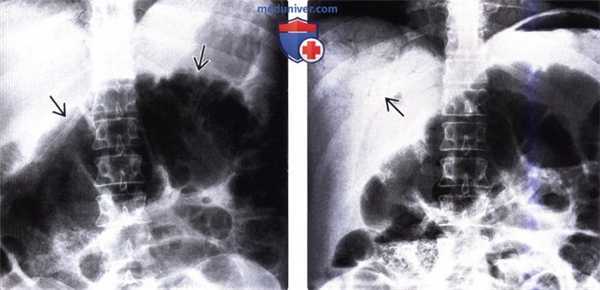

(Слева) На рентгенограмме в передне-задней проекции в положении пациента лежа на спине визуализируется растянутая газом толстая кишка в верхних отделах брюшной полости, левая часть которой располагается наиболее высоко.

(Справа) На рентгенограмме в передне-задней проекции у этого же пациента определяется газ в печени (в периферических ветвях воротной вены). Во время операции обнаружился заворот слепой кишки и ее брыжейки, осложненный ишемическим некрозом ее стенки.